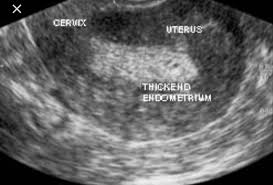

How To Know If You Have Endometrial Cancer - Uterine Cancer General Information Symptoms Signs Of Endometrial Cancer Cleveland Oh University Hospitals : Symptoms of uterine cancer that are different from uterine fibroids include abnormal vaginal bleeding (bleeding that is not part of a menstrual period, bleeding after menopause), or a mass in the vagina.. Until then, you might try to: Most endometrial cancer recurrences are found because of symptoms, so it's very important that you tell your doctor exactly how you're feeling. Endometrial cancer (more common) and uterine sarcoma. Endometrial cancer begins in the layer of cells that form the lining (endometrium) of the uterus. It is usually done in your doctor's office.

Doctors recommend this if you no longer want to become pregnant. _____american cancer society cancer.org | 1.800.227.2345 is there a chance i don't have cancer? By far the more common type is endometrial cancer, or cancer of the uterine lining (the endometrium). I wish i had any other inflammation in my body but i don't. It would take 800 days to grow to 100 cells — far too small for detection, let alone symptoms. Know the signs and symptoms of endometrial cancer. The most likely symptoms are: The same process for the original endometrial cancer diagnosis, will apply again. When cancer cells do this, it's called metastasis. Find out enough about endometrial cancer to make decisions about your care. How does the doctor know i have endometrial cancer?€€ endometrial cancer may be found after a woman goes to a doctor because she has Bleeding may be abnormal because of how heavy it is or when it happens, such as after you have gone through menopause, between periods, or any other bleeding that is longer or heavier than is normal for you. Endometrial biopsy is often a very accurate way to diagnose uterine cancer.

Atypical types of endometrial hyperplasia, especially complex, increase your risk of getting cancer. However, it is distinct from other types of uterine cancer such as uterine sarcoma, cervical cancer, and trophoblastic disease. Every person eventually finds a way to cope with an endometrial cancer diagnosis. These tests can be used to help diagnose or rule out uterine cancer. Endometrial cancer is often referred to as uterine cancer. How does the doctor know i have endometrial cancer?€€ endometrial cancer may be found after a woman goes to a doctor because she has Coughing up mucus tinged with blood blood in stools or urine lump in the. Know the signs and symptoms of endometrial cancer. Uterine cancer includes two types of cancer: A d&c is a procedure to remove tissue samples from the uterus. If symptoms or the physical exam suggests the cancer might have come back, imaging tests (such as ct scans or ultrasounds), a ca 125 blood test, and/or biopsies may be done. Uterine cancer symptoms include bleeding between periods or after menopause. Endometrial cancer is sometimes called uterine cancer.

Treatment Options For Endometrial Cancer Cancer Australia from img.yumpu.com The most common symptom of endometrial cancer is abnormal vaginal bleeding. If endometrial cancer is found after examining uterine tissue samples, further tests may be done to see if the cancer cells have spread within the uterus or to other parts of the body. Coughing up mucus tinged with blood blood in stools or urine lump in the. So even if endometrial cancer spreads to the liver (or any other place), it's still called endometrial cancer. If the uterus has become enlarged due to the cancer, you. Your doctor may do this test in his or her office, or may refer you to another doctor. Would you please write down the kind of cancer you think i might have? Endometrial biopsy is often a very accurate way to diagnose uterine cancer.